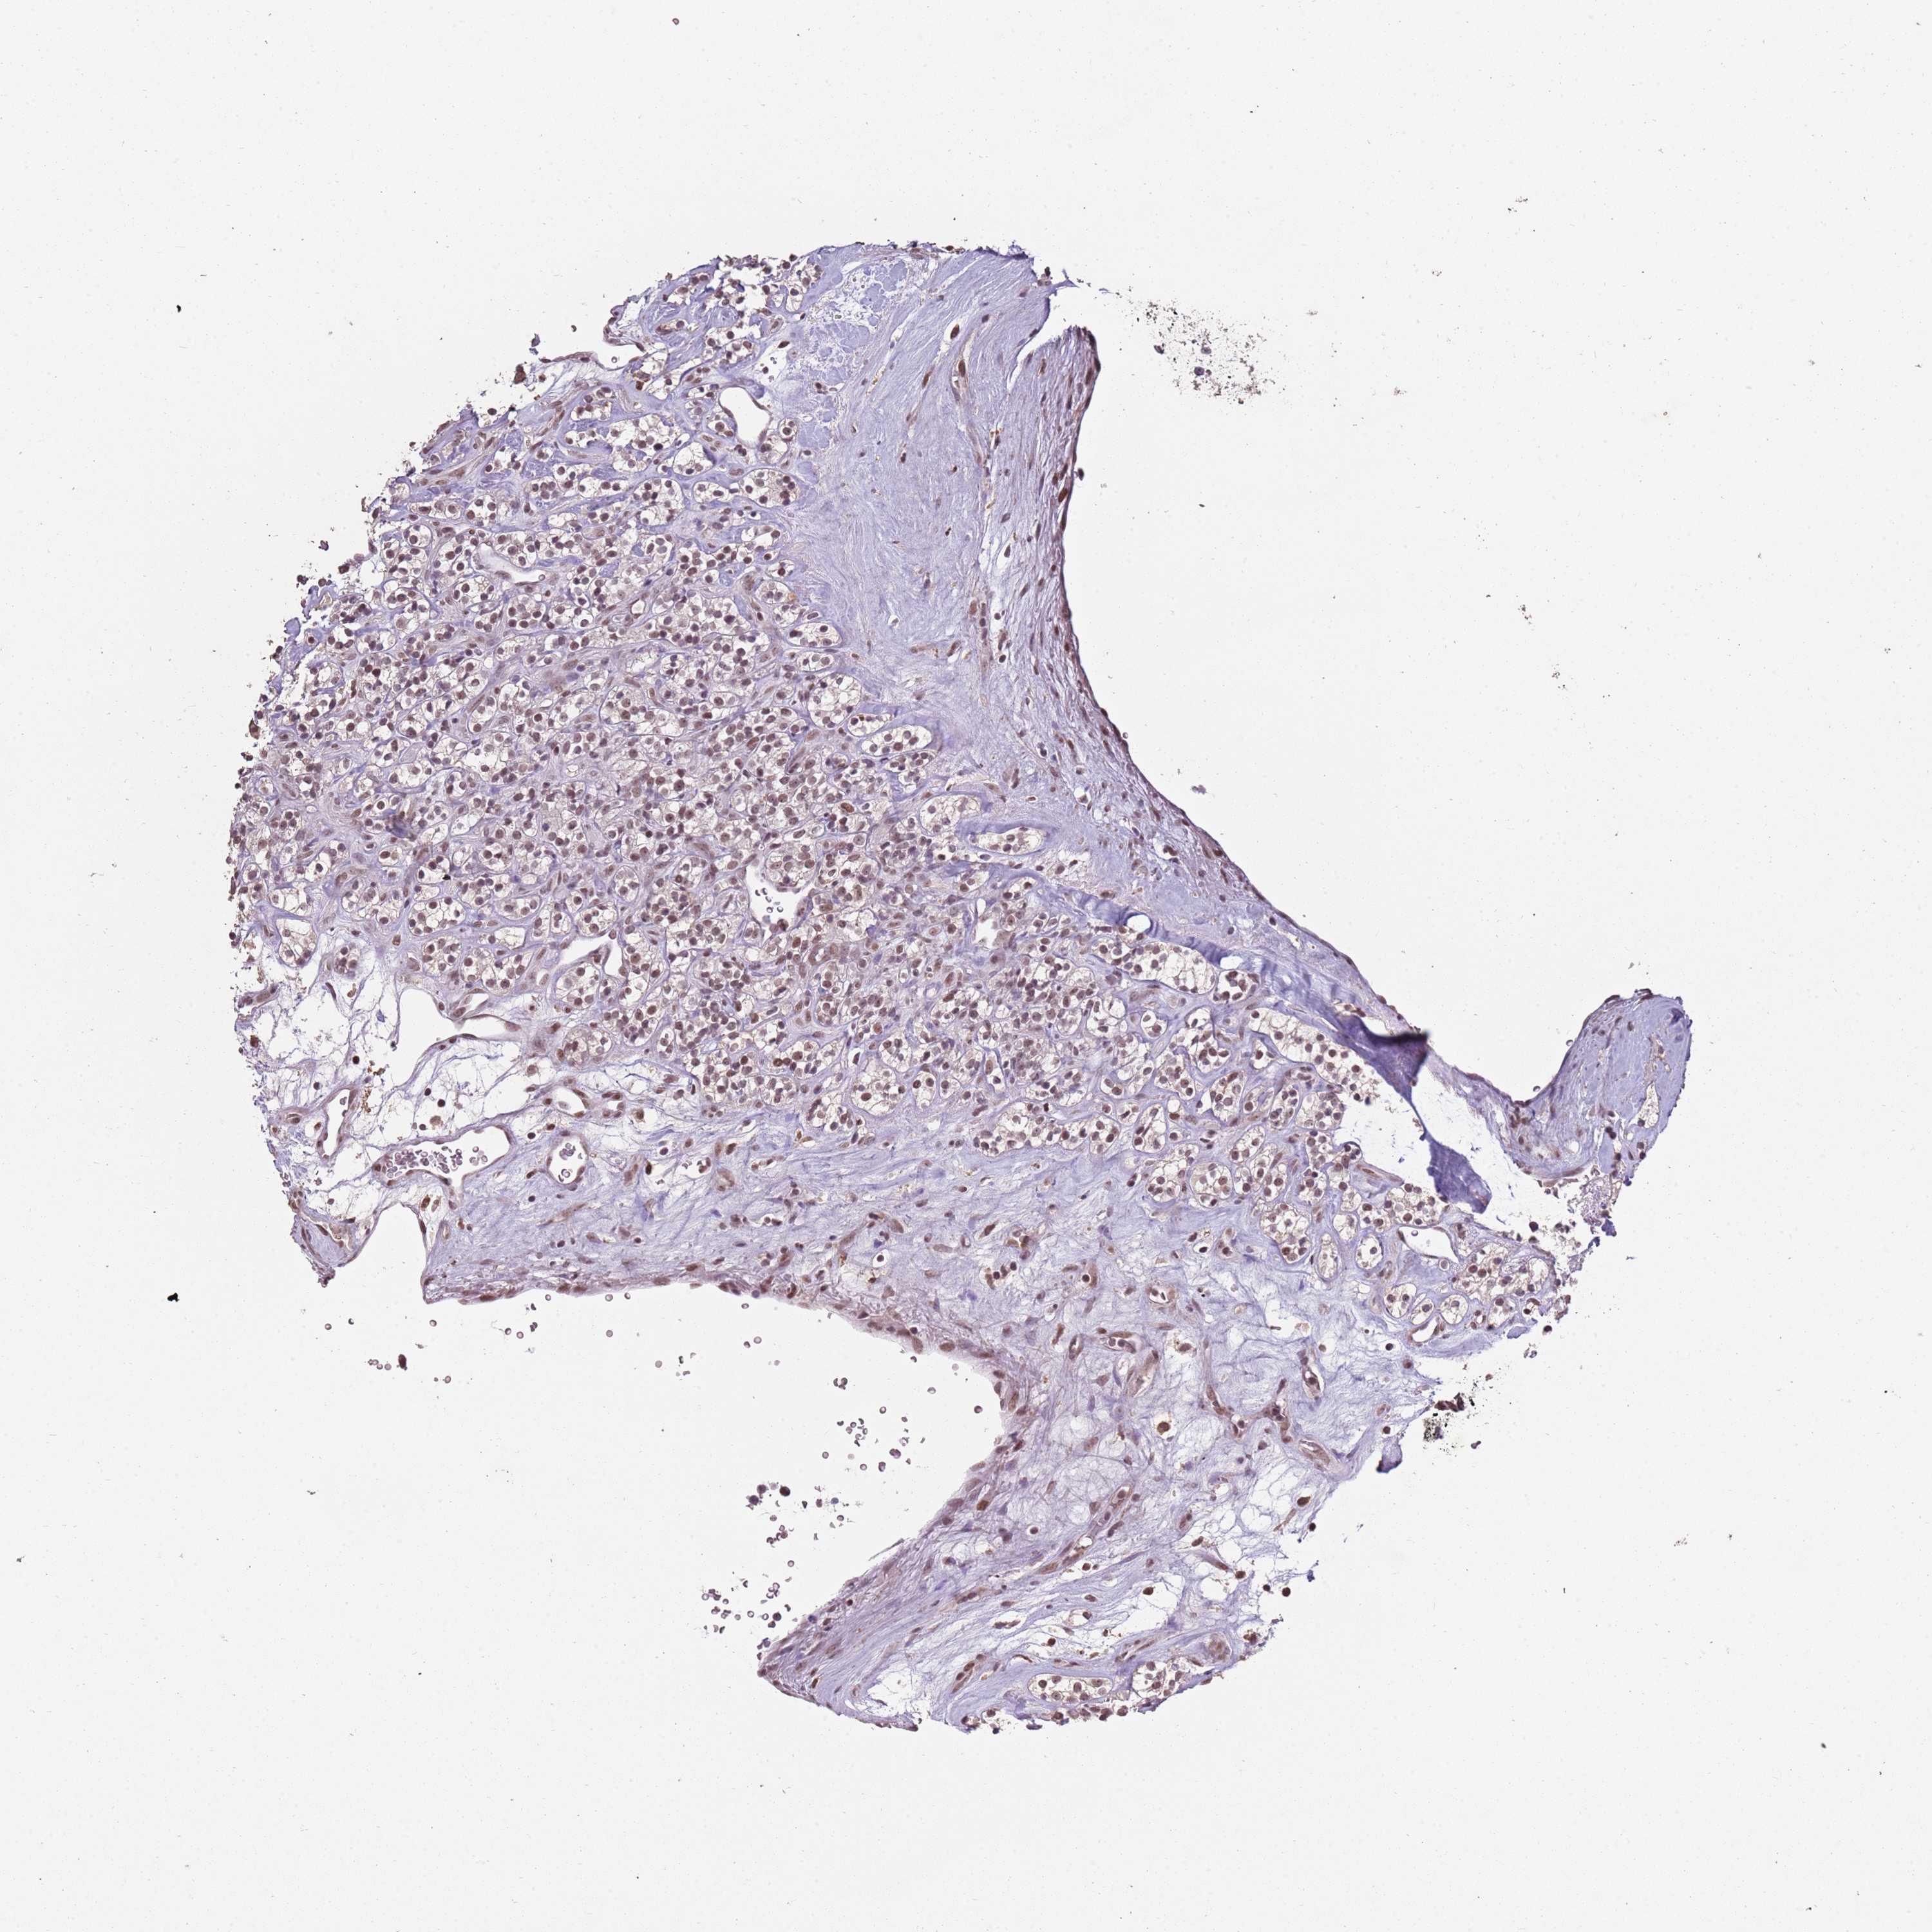

ARL14EP is not prognostic in Kidney Chromophobe (TCGA)

Best expression cut offi

: 21.36

P scorei

N/A

5-year survival highi

5-year survival lowi

Average pTPM 15.4

Number of samples 64